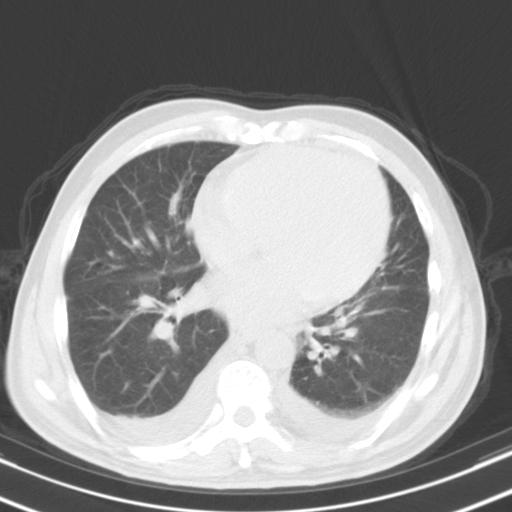

以下是引用zxl51642在2010-3-21 17:06:00的发言:[br]右下中心型肺癌并阻塞性肺炎/不张,纵膈淋巴结肿大,右侧大量胸腔积液,左侧少量胸腔积液,少量腹水。建议纤维支气管镜进一步检查。